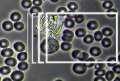

コントラスト(明暗)の高い立体感の有る画像で、赤血球などを観察すると重なり具合や形状が鮮明に映し出されます。

微小細菌や輪郭のはっきりしない物体も染色しなくても鮮明に観察可能です。

色彩はモノトーン(白黒)となり、本来の色は反映されません。 |

| 血液 |